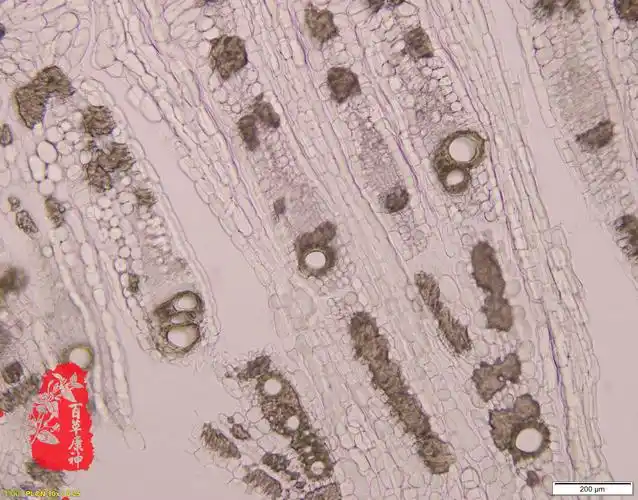

甘草粉末特征黄芪粉末特征(导管,纤维,淀粉粒,木栓细胞)